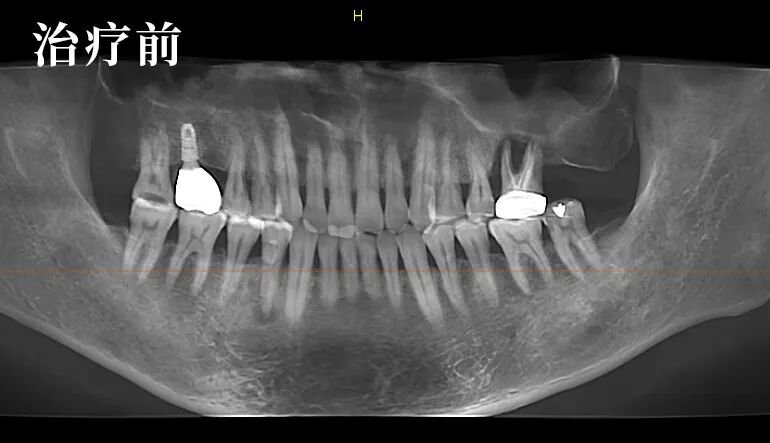

经过详细的检查及影像对比,朱医生发现了问题的特殊性:局部的炎症并非疼痛的主因,真正的问题在于患者自身双侧关节的先天不对称,导致了咬合力的异常分布。

这是一个典型的“继发性问题”——原有的修复体与患者独特的生理结构之间,产生了需要精细调整的力学冲突。

他邀请李先生一同观看影像,耐心解释道:“您看,问题的核心在于关节的先天条件导致了力量失衡。我们的目标不是简单地为你消炎,而是为您重建一个专属的、稳定的咬合平衡。”

这是一个为李先生量身定制的方案:待软组织充分恢复后,通过重新取模和精细的牙合调整,制作能适应其独特关节结构的新修复体。